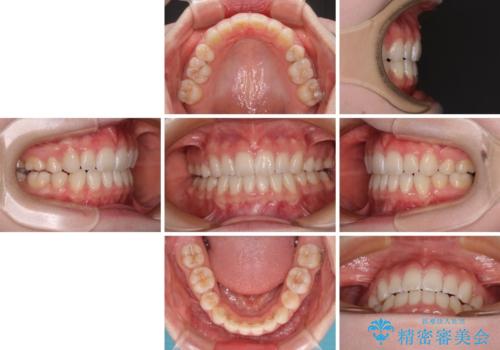

- 前歯の出っ歯と口元の閉じにくさを気にして来院された患者様です。

口元を積極的に引っ込めるために、上下左右の小臼歯4本を抜歯することとしました。

4本の歯を抜歯したことで、飛び出していた口元が引っ込み、横顔が大きく改善されました。